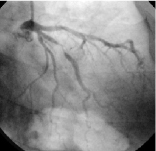

同じ患者様のカテーテル検査の写真です。(CTと同じ所に狭い部分があります) -

狭くなっている部分にステントと呼ばれる金属の筒を入れて血管の流れが良くなりました。